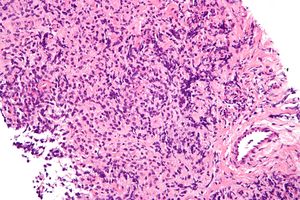

| صورة مجهرية للمفوما الخلية البائية الضخمة المنصفية الأولية، نوع من اللمفوما ضخمة الخلية، H&E stain. | |

تبعاً لأحد نظم تصنيف اللمفومات، يتم تقسيم الأمراض تبعاً لحجم خلايا الدم البيضاء التي تحولت لخلايا سرطانية. اللمفومات ضخمة الخلية تتضمن خليا ضخمة. في هذا السياق، يبلغ قطر الخلية الضخمة من 17 إلى 20 ميكرومتر.[1] مجموعات اللمفومات الأخرى في هذا النظام هي اللمفومات صغيرة الخلية واللمفومات مختلطة الخلية.